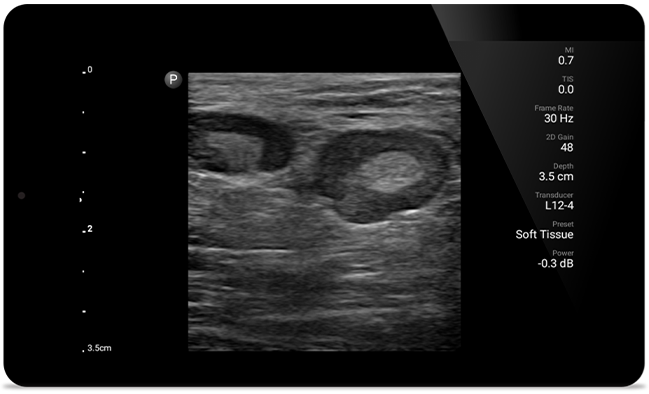

Lumify helps you see the fine details in muscles, joints, ligaments, tendons and cartilage to make a more accurate diagnosis of injuries.

Get the clarity of larger ultrasound systems with Lumify

SonoCT reinforces real tissue imaging while eliminating random artifacts. This technology produces images superior to conventional imaging in up to 94% of patients.

• 5 to 2 MHz extended operating frequency range • 50mm radius of curvature • 2D, color Doppler, M-mode, advanced XRES and multivariate harmonic imaging, SonoCT • High-resolution imaging for deeper applications: abdominal, gall bladder, OB/GYN and lung imaging preset optimizations